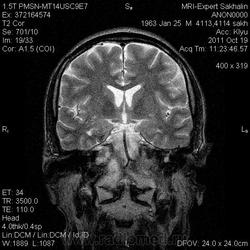

объемное образование ската с распространением на пирвмидку височной кости, область атланто-окципитального сочленения, не выраженно контрастируется- может хордома?-хотя сиггнал по Т2 для нее не типичен ( более характерен гиперинтенсивный МРС) Но ведь возможны вариации?. А КТ не делали?.

Мне тоже показалось, что хордома)))